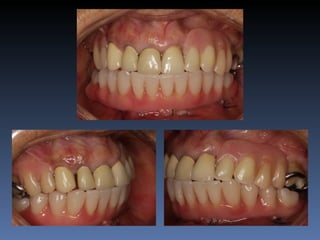

Maurício Zanetti

Idade – 47 anos

Sexo – Masculino

Raça – Caucasiana

ASA – II

Data- 25-04-2012

Diagnóstico: Desdentado parcial

pré-maxila.

Plano de tratamento: Reabilitação pré-maxila com

instalação de 2 implantes endo-ósseos (1.1,.2.2), para

reabilitação protética fixa.